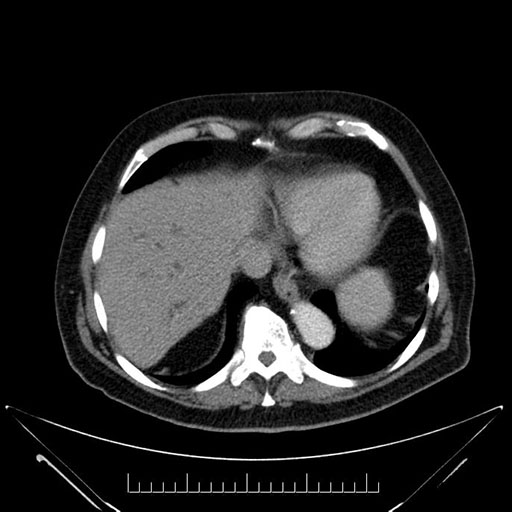

Axial - 3 months prior